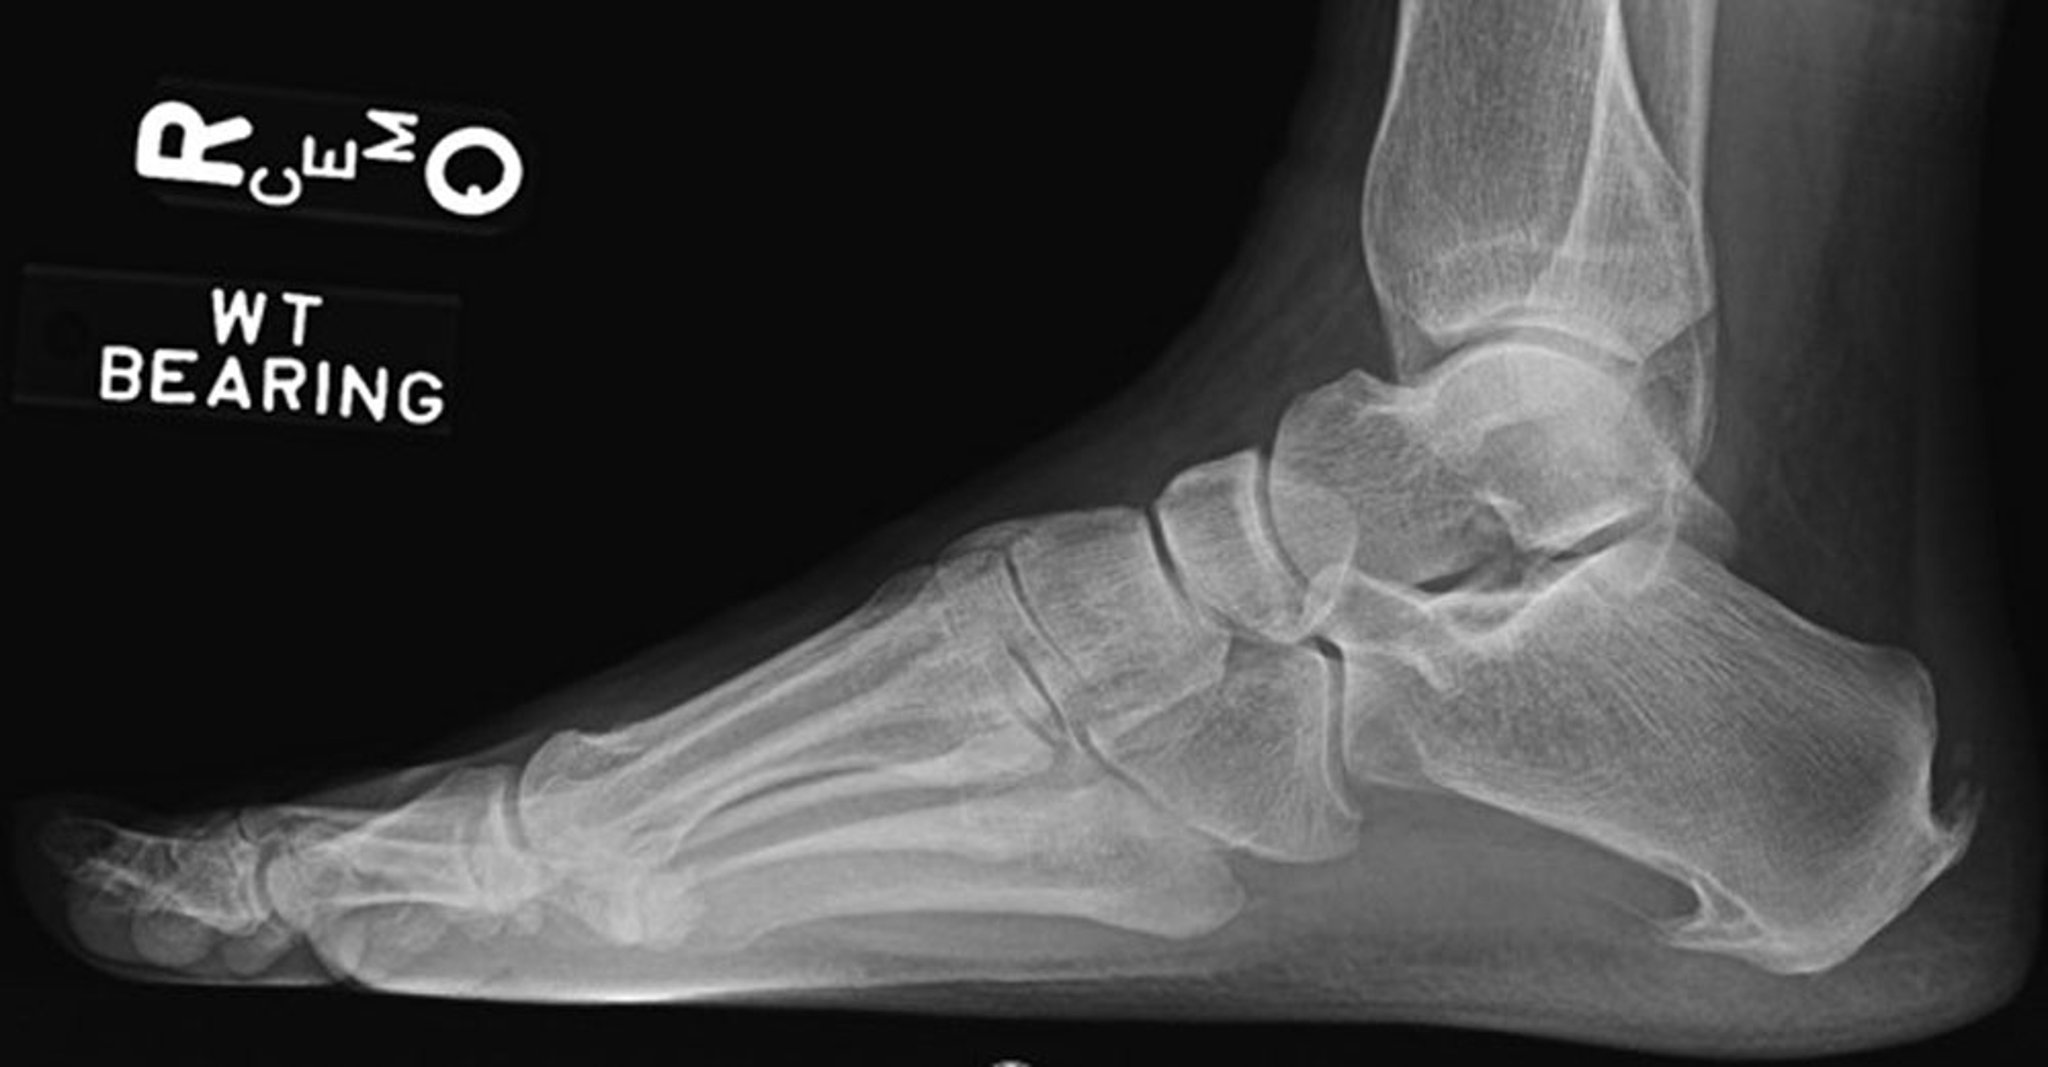

Plantar fasciitis is confirmed if pain is elicited when firm thumb pressure is applied to the calcaneus when the foot is dorsiflexed. Fascial pain along the plantar medial border of the fascia may also be present. If findings are equivocal, demonstration of a heel spur on radiograph may support the diagnosis; however, absence does not exclude the diagnosis, and visible spurs are not generally the cause of plantar fasciitis symptoms. Also, infrequently, calcaneal spurs appear ill defined on radiographs, exhibiting fluffy new bone formation, suggesting spondyloarthropathy (eg, ankylosing spondylitis, reactive arthritis). If an acute fascial tear is suspected, MRI is indicated.

Image courtesy of James C. Connors, DPM.